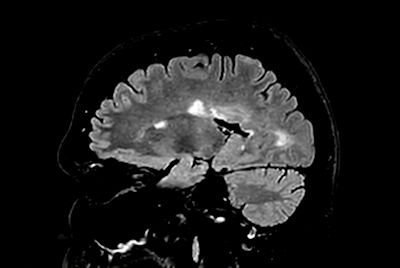

Brain - White matter lesions